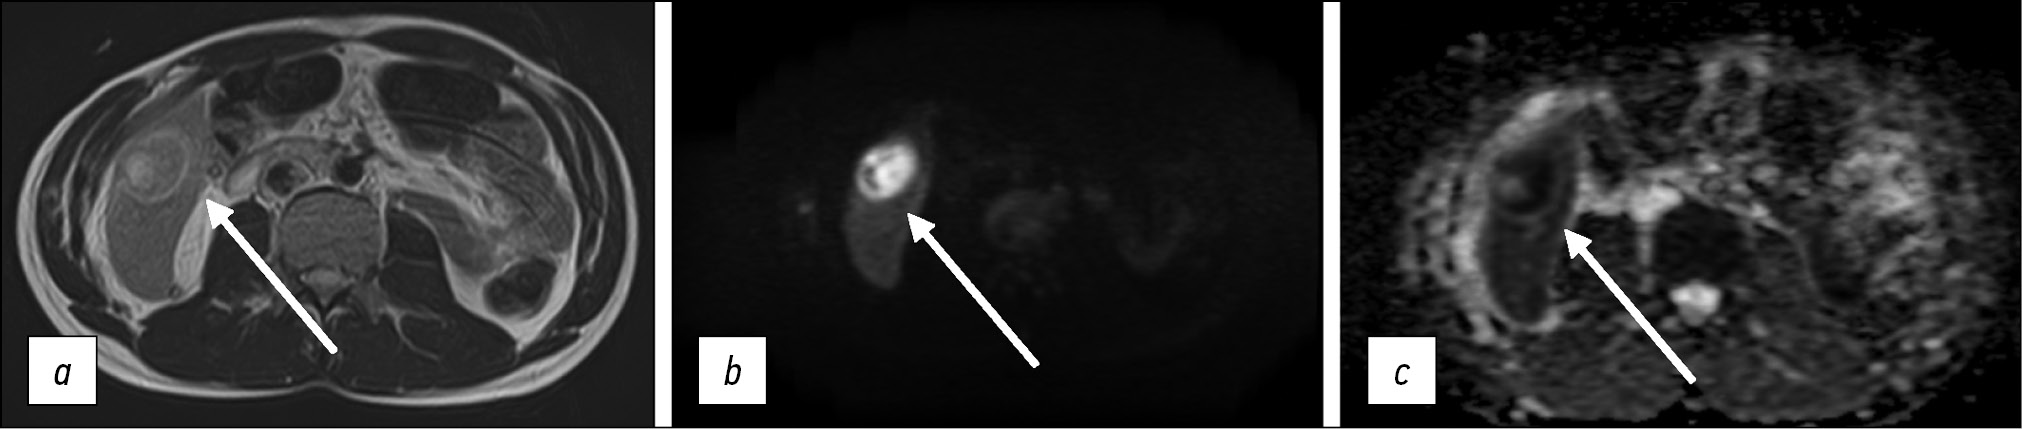

For a more accurate assessment of hepatic steatosis or signs of hemochromatosis, in-phase and opposed-phase T1-WIs should also be included in the standard MRI protocol. Furthermore, this sequence is useful in the diagnosis of adrenal adenoma (Fig. 6), clear-cell renal cell carcinoma, and pancreatic fatty infiltration (Fig. 7). These sequences must be obtained before contrast agent injection. Out-of-phase images allow for the assessment of signal loss from adipose tissue and fat-containing lesions such as liver adenomas or hepatocellular carcinoma. Moreover, the determination of the proton density fat fraction is the gold standard for noninvasive quantitative assessment of hepatic steatosis. However, this sequence is not included in the routine protocol.

Figure 6. Abdominal computed tomography, axial plane (а): a right adrenal mass of nonuniform density is visualized (arrow); abdominal magnetic resonance imaging (b, с), in-phase (b) and opposed-phase (с): a typical signal loss from the adenoma fat component in the opposed-phase is detected (arrows).